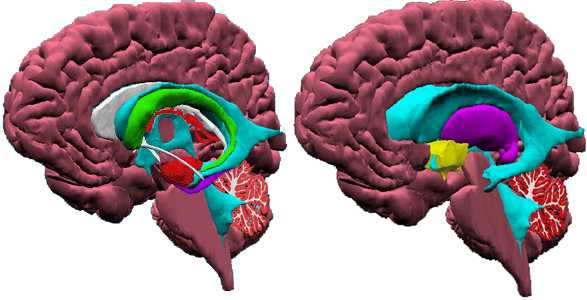

El Sistema Nervioso es, junto con el Sistema Endocrino, el rector y coordinador de todas las actividades, conscientes e inconscientes del organismo, consta del sistema cerebroespinal (encéfalo y médula espinal), los nervios y el sistema vegetativo o autónomo.

El Cerebro es el órgano clave de todo este proceso. Sus diferentes estructuras rigen la sensibilidad, los movimientos, la inteligencia y el funcionamiento de los órganos. Su capa más externa, la corteza cerebral, procesa la información recibida, la coteja con la información almacenada y la transforma en material utilizable, real y consciente.

El Cerebro es el órgano clave de todo este proceso. Sus diferentes estructuras rigen la sensibilidad, los movimientos, la inteligencia y el funcionamiento de los órganos. Su capa más externa, la corteza cerebral, procesa la información recibida, la coteja con la información almacenada y la transforma en material utilizable, real y consciente.El Sistema Nervioso permite la relación entre nuestro cuerpo y el exterior, además regula y dirige el funcionamiento de todos los órganos del cuerpo.

Es la masa nerviosa contenida dentro del cráneo. esta envuelta por las meninges, que son tres membranas llamadas: duramadre, piamadre y aracnoides. El encéfalo consta de tres partes más voluminosas: cerebro, cerebelo y bulbo raquídeo, y otras más pequeñas: el diéncéfalo, con el hipotálamo (en conexión con la hipófisis del Sistema Endocrino) y el mesencéfalo con los tubérculos cuadrigéminos.

- El cerebro:

Es la parte más importante, está formado por la sustancia gris (por fuera) y la sustancia blanca (por dentro). Su superficie no es lisa, sino que tienes unas arrugas o salientes llamadas circunvoluciones; y unos surcos denominados cisuras, las más notables son llamadas las cisuras de Silvio y de Rolando. Esta dividido incompletamente por una hendidura en dos partes, llamados hemisferios cerebrales. En los hemisferios se distinguen zonas denominadas lóbulos, que llevan el nombre del hueso en que se encuentran en contacto (frontal, parietal...). Pesa unos 1.200gr Dentro de sus principales funciones están las de controlar y regular el funcionamiento de los demás centros nerviosos, también en el se reciben las sensaciones y se elaboran las respuestas conscientes a dichas situaciones. Es el órgano de las facultades intelectuales: atención, memoria, inteligencia ... etc.

- El cerebelo:

Esta situado detrás del cerebro y es más pequeño (120 gr.); tiene forma de una mariposa con las alas extendidas. Consta de tres partes: Dos hemisferios cerebelosos y el cuerpo vermiforme. Por fuera tiene sustancia gris y en el interior sustancia blanca, esta presenta una forma arborescente por lo que se llama el árbol de la vida. Coordina los movimientos de los músculos al caminar y realizar otras actividades motoras.

- El bulbo raquídeo:

Es la continuación de la médula que se hace más gruesa al entrar en el cráneo. Regula el funcionamiento del corazón y de los músculos respiratorios, además de los movimientos de la masticación, la tos, el estornudo, el vómito ... etc. Por eso una lesión en el bulbo produce la muerte instantánea por paro cardiorespiratorio irreversible.

- La médula espinal:

La médula espinal es un cordón nervioso, blanco y cilíndrico encerrada dentro de la columna vertebral. Su función más importante es conducir, mediante los nervios de que está formada, la corriente nerviosa que conduce las sensaciones hasta el cerebro y los impulsos nerviosos que lleva las respuestas del cerebro a los músculos.

Atlas visual del cerebro

Atlas anatómico del cerebro con imágenes y explicaciones de sus principales componentes.

Selecciona la zona del cerebro que quieras consultar o haz click en el enlace que se muestra más abajo para obtener información ampliada de la función de cada una de las partes del cerebro.